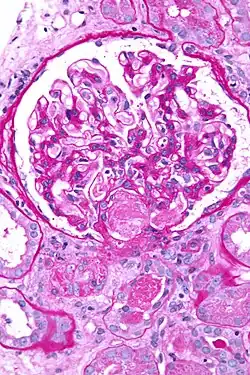

Micrograph showing acute thrombotic microangiopathy due to DIC in a kidney biopsy. A clot is present in the hilum of the glomerulus (center of image).